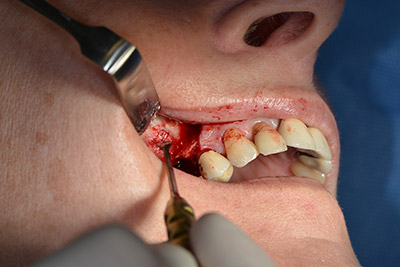

The next step was the sinus floor elevation with simultaneous implantation. The Implantmed also had a presetting at the first position for the buccal fenestration of the maxillary sinus wall.

The fenestration was prepared at 35,000 rpm and then the nasal mucosa were prepared in the cranial direction (Fig. 13 to 14).

The implant was then placed and the bone built up. In this case, because of the size of the augmentation region, autologous bone chips, harvested with an osseous trap as drilling chips from implantation 16 and fenestration 14, were mixed with bone replacement material.

An absorbable membrane was used as the barrier in the buccal direction and covered the augmentation. Finally, saliva-proof sutures were placed (Fig. 15 to 19).